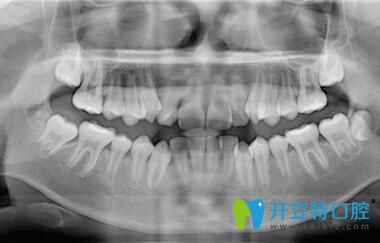

深圳正夫口腔的正畸醫(yī)生面診后,說我的牙齒屬于牙列不齊、前牙擁擠;針對我的情況,又拍了牙片;然后才制定矯正方案,建議戴傳統(tǒng)金屬托槽或球面自鎖托槽,也把這兩種牙套的優(yōu)缺點(diǎn)和價格都做了詳細(xì)的介紹。